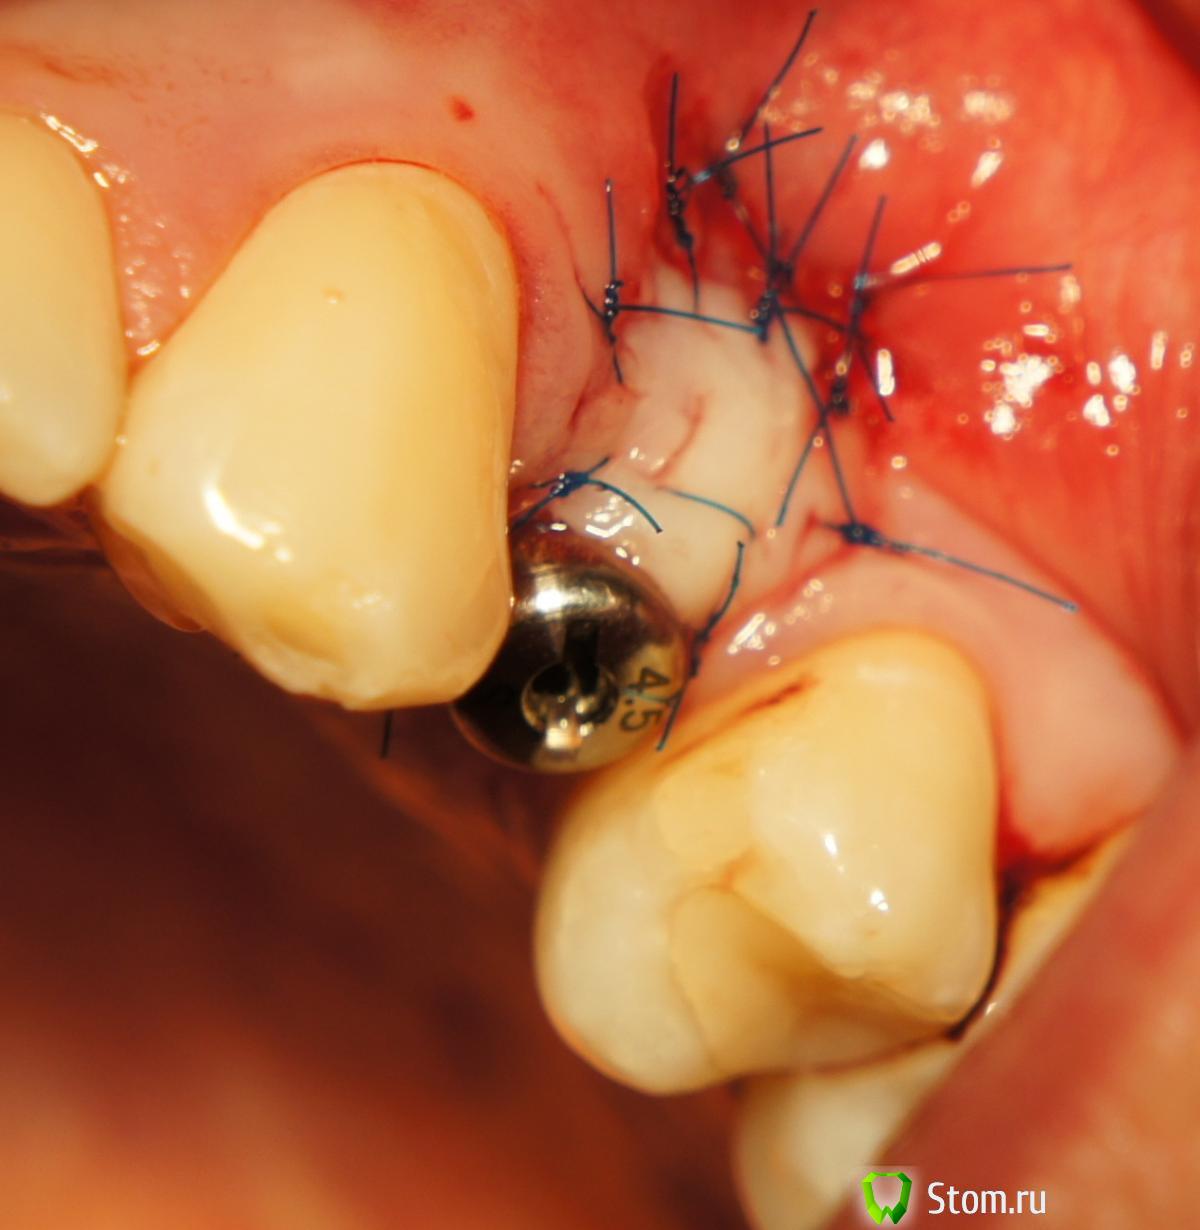

FBR Опубликовано 12 апреля, 2012 Поделиться Опубликовано 12 апреля, 2012 Добрый день коллеги! Провел пластику СДТ в области 24. Буду признателен за комментарии и советы. (извините за качество фотографий, я только начал. В последствии исправлюсь...). Ссылка на комментарий

FBR Опубликовано 12 апреля, 2012 Автор Поделиться Опубликовано 12 апреля, 2012 (изменено) Объем добавить хотелось, и прикрепленную десну Изменено 12 апреля, 2012 пользователем FBR Ссылка на комментарий

Sahan Опубликовано 14 апреля, 2012 Поделиться Опубликовано 14 апреля, 2012 надо было перетащить кусок десны с нёба апикальным смещением, а для объема сунуть под него ССТ. В данном случае лоскут на ножке ножке теряет смысл из за слишком маленького расстояния между зубами. СДТ больше подходит. Вот если бы это был концевой дефект или межзубное расстояние побольше , тогда да. Ссылка на комментарий

Большой Зеленый Опубликовано 14 апреля, 2012 Поделиться Опубликовано 14 апреля, 2012 Помрет СДТ с соплями и некрозом ,имхо.. Ссылка на комментарий

Большой Зеленый Опубликовано 15 апреля, 2012 Поделиться Опубликовано 15 апреля, 2012 Этот помрет. Надо было его не пришивать рядом ,а укрывать как у Стаси с соседней теме Ссылка на комментарий